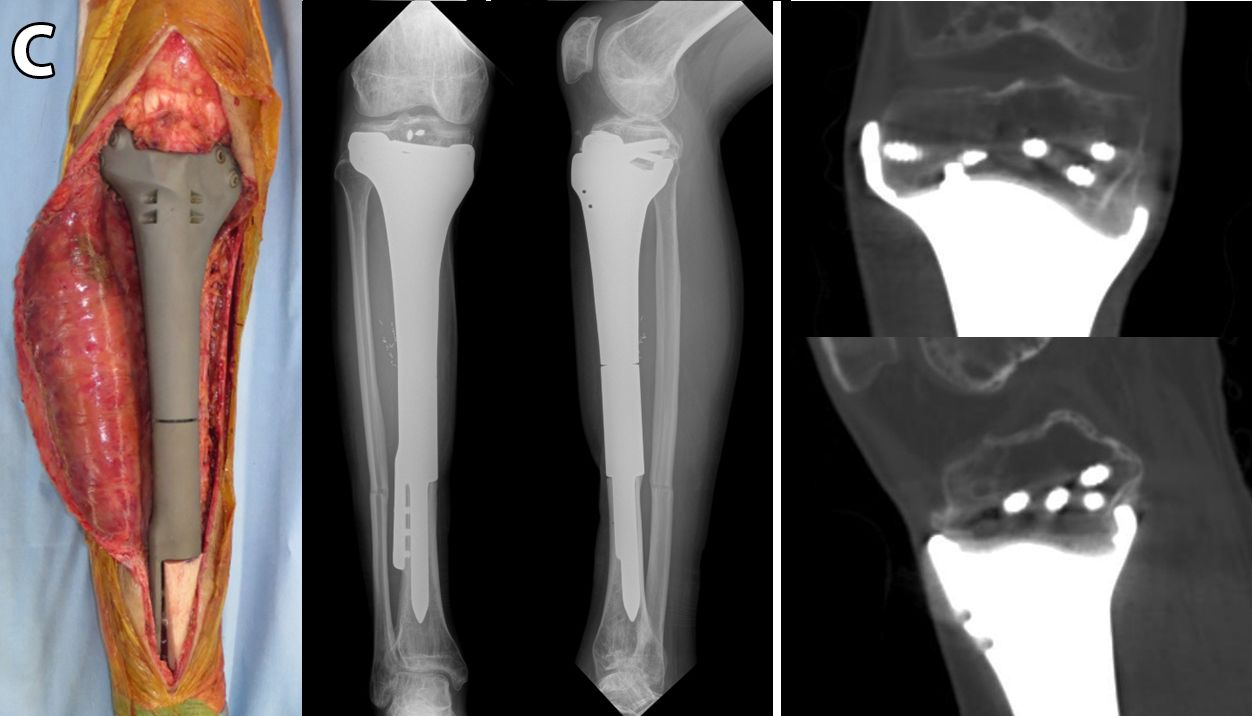

At variance with all other existing antibacterial coating technologies, the DAC® hydrogel has been designed to offer an “ALL IMPLANT(S)” coating ability and can be used to protect various surfaces, including titanium alloys, nickel-chrome, cobalt-chrome, stainless steel, hydroxyapatite, polyethylene or other polymeric biomaterials (Fig. 3).

The hydrogel is not designed and should not be mixed with bone cement or its components (polymethylmethacrylate, PMMA) until they have finished their exothermal reaction and have completely hardened. The ability of DAC® hydrogel to completely cover even sand-blasted titanium surface and resist scraping has been confirmed by scanning electron microscopy (SEM) analysis [48]. Moreover, the DAC® coated implants can be press-fit inserted with the usual surgical technique. The resistance to scraping and de-clothing has been tested in the animal models and in human femurs, simulating a press-fit insertion of a cementless implant [49]. Both studies demonstrated the ability of the hydrogel coating to resist insertion, with approximately 60% to 80% of the hydrogel remaining adherent to all the implant surface, while the remainder being retrieved along the inner surface of the medullary canal.

In line with the concept of “ALL IMPLANT” coating, primary or revision cementless or hybrid joint prostheses and all internal osteosynthesis, including plates, screws and intramedullary nails, the surface in contact with the bone and all the modular parts, the polyethylene insert, the screws, sleeves, pegs, etc. and the respective locking mechanisms, should be protected with the hydrogel coating (Fig. 3).

Although the protection of the intra-medullary parts of an implant is pivotal, in order to prevent bacterial adhesion and proliferation at the implant-bone interface, defending the extra-medullary parts of the implant may be equally beneficial to reduce the chance of bacterial adherence and progressive colonization.